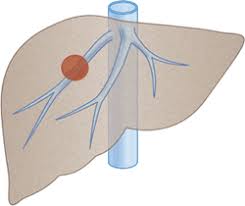

1. 간암이란?

(1) 정의와 구분

① 간암은 간에 발생하는 악성 종양으로, 크게 원발성 간암과 전이성 간암으로 나뉩니다.

② 원발성 간암은 간세포에서 직접 발생하며, 대표적인 형태는 간세포암종(HCC, Hepatocellular Carcinoma)입니다.

③ 전이성 간암은 위, 대장, 폐 등 다른 기관에서 발생한 암이 간으로 전이된 것입니다.